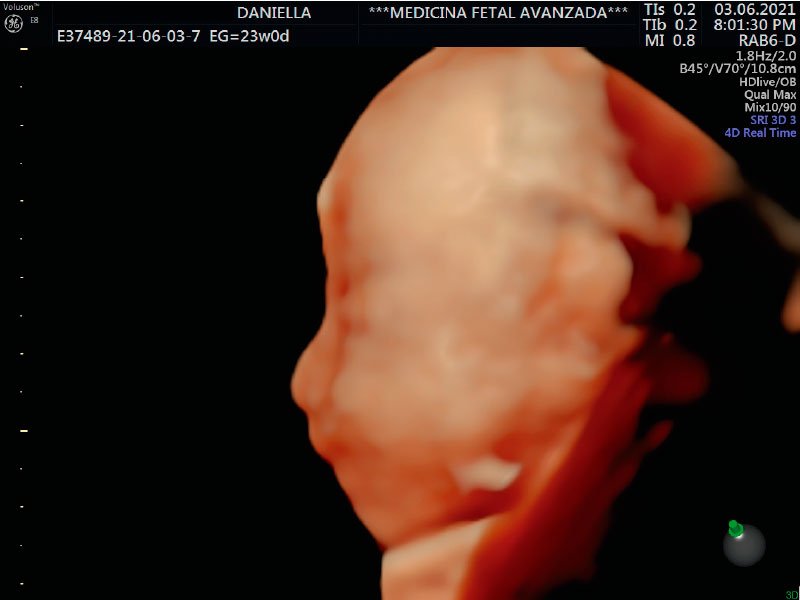

Ahora estamos en la semana 24 de este par de mellizos que esperamos recibir en septiembre.